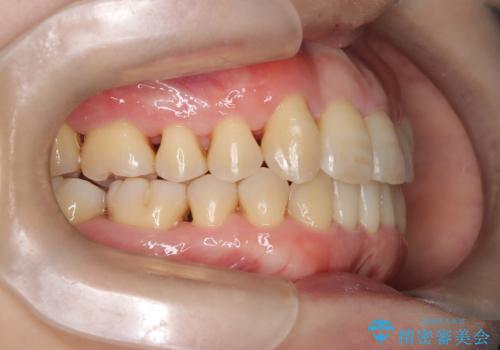

【インビザライン】ずれた前歯の噛み合わせをなおしたい

- 前歯の噛み合わせが悪いことを主訴に来院されました。

歯周病も併発していたため、歯牙への負担が少なくなるように治療計画をたて、インビザラインにて治療を完了しました。

矯正開始前に半年間、歯周治療を行ってからインビザラインを装着しています。